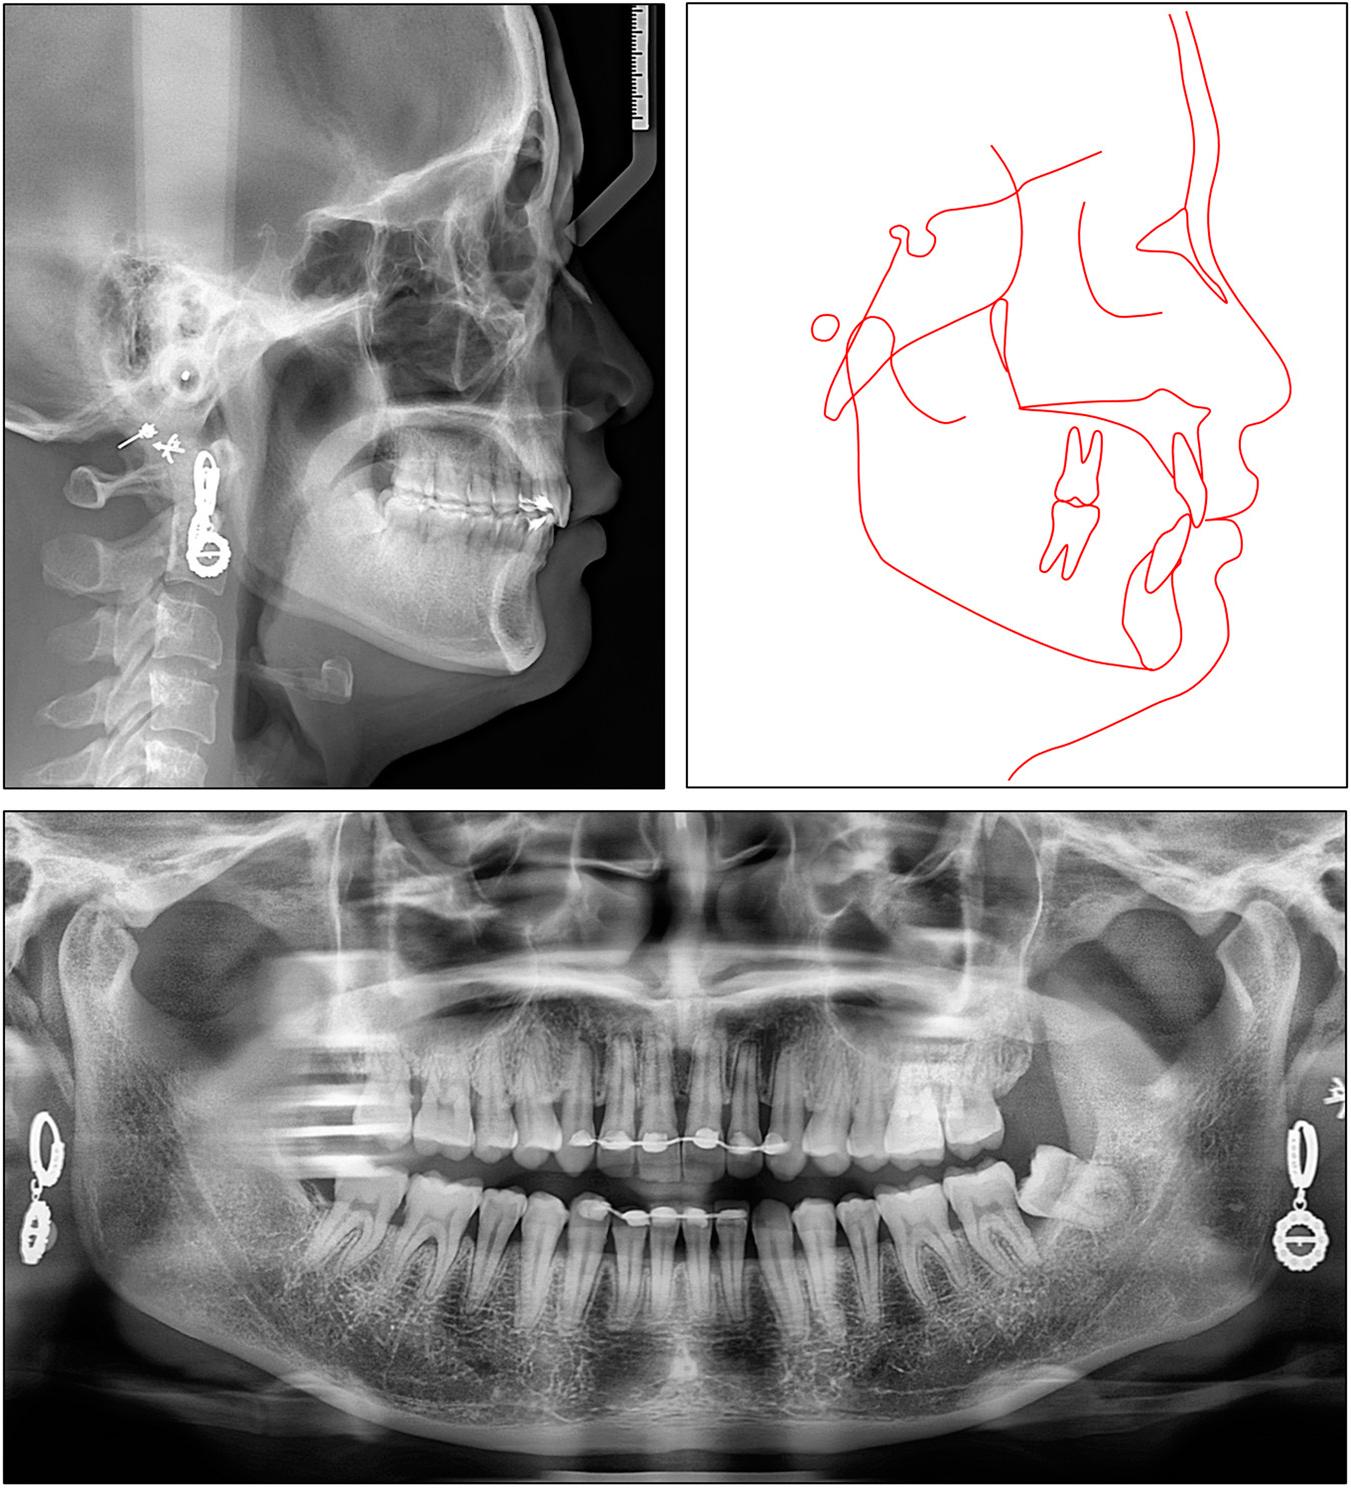

Figure 4.

Cephalometric measurements of case 2

| Pretreatment | Posttreatment | |

|---|---|---|

| Skeletal | ||

| SNA (°) | 85.5 | 83.0 |

| SNB (°) | 75.8 | 75.0 |

| ANB (°) | 9.7 | 8.0 |

| FMA (°) | 21.4 | 22.1 |

| Dental | ||

| U1-SN (°) | 73.9 | 94.1 |

| U1-PP (°) | 83.1 | 104.3 |

| U1-NA (°) | -11.7 | 11.1 |

| U1-NA (mm) | -5.7 | -2.2 |

| IMPA (°) | 103.4 | 106.0 |

| L1-NB (°) | 29.4 | 33.0 |

| L1-NB (mm) | 5.3 | 6.8 |

| Interincisal angle (°) | 152.5 | 127.9 |

| Upper incisal display (mm) | 3.7 | 2.3 |

| Soft tissue | ||

| E-line/UL (mm) | 1.9 | -1.5 |

| E-line/LL (mm) | 0.2 | -0.9 |